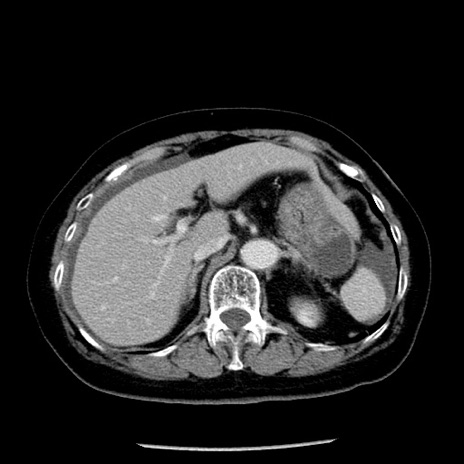

症例13(横断像)

【症例】70歳代女性

【主訴】腹痛、嘔吐

【現病歴】15時間程前(昨晩)より腹痛あり。今朝になっても症状の改善なく、嘔吐あり。腹痛も増悪あり、救急外来受診。

【既往歴】子宮癌全摘術後

【身体所見】意識清明、BP 121/72mmHg、P 74bpm、SpO2 100%(RA)、腹部:平坦・軟、腸雑音ほぼ聴取せず。下腹部・心窩部・臍左上に圧痛あり。反跳痛なし。

【データ】WBC 10600、CRP 0.15